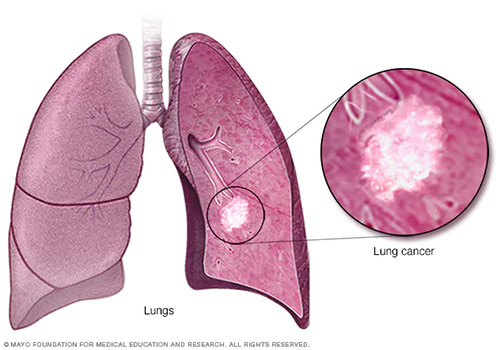

Tumors & Cancers

Lung And Other Respiratory Conditions